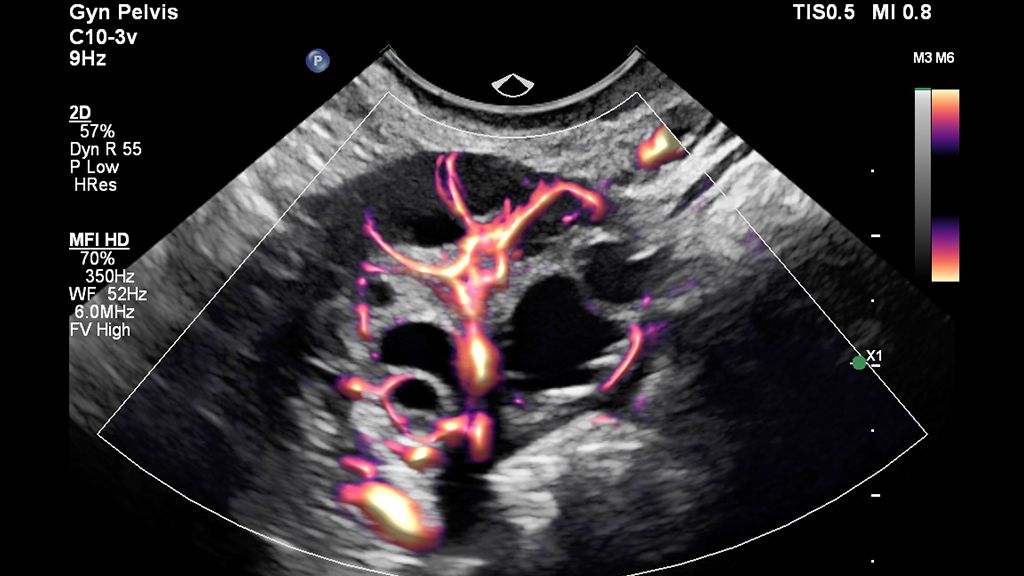

• Clinical image of pelvis scanned with MFI HD using EPIQ Elite and C10-3v transducer

MFI HD with Flow Viewer image of the ovary